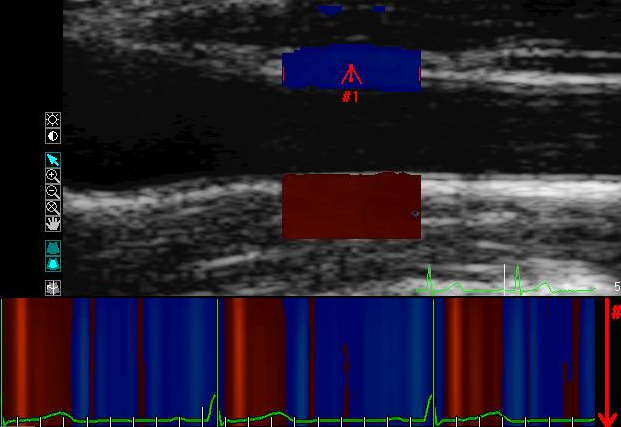

100, %, где:

D - показатель абсолютного систоло-диастолического прироста диаметра = (Ds –Dd), ln – натуральный логарифм, Ps – систолическое артериальное давление, Pd – диастолическое артериальное давление, Ds – сиcтолический диаметр, Dd – диастолический диаметр, IMT – толщина комплекса интима-медиа (ТИМ) в диастолу.Методика импульсно-волновой допплерографии (ТД). Анализ движения артериальной стенки проводился с синхронной записью ЭКГ при задержке дыхания пациента на протяжении 5-10 сердечных циклов. Контрольный объем размещался в области передней и задней стенки на участке 2 -3 cm проксимальнее бифуркации ОСА и ОБА. Точкой начала отсчета временных фаз считали зубец R-ЭКГ. Проводился анализ следующих параметров ТД передних и задних стенок правых ОСА и ОБА: Vsmax (см/с) – максимальная скорость антеградного пика движения стенки в фазу систолы, Vdmax (см/с) – максимальная скорость ретроградного пика движения стенки в фазу диастолы, Vs/Vd – показатель отношения скорости антеградного пика к скорости ретроградного, TR-Vs (мс) - время от вершины зубца R-ЭКГ до начала антеградного систолического пика, TR-Vd (мс) – время от вершины зубца R-ЭКГ до начала ретроградного диастолического пика (рис.1.А.Б.). Максимальные систолические и диастолические скорости стенок ОСА и ОБА корректировались к пульсовому давлению и диастолическому диаметру (Steinbach J.C. 2003), в результате чего получали их относительные значения: Vsmaxrel = Vsmax/(ПАД∙Dd)∙10, относительный показатель систолической скорости; Vdmaxrel = Vdmax/(ПАД∙Dd)∙10, относительный показатель диастолической скорости.

А.

Б.Рис.1. График скорости движения передней стенки ОСА (А) и ОБА (Б) по данным импульсно-волновой тканевой допплерографии (ТД).